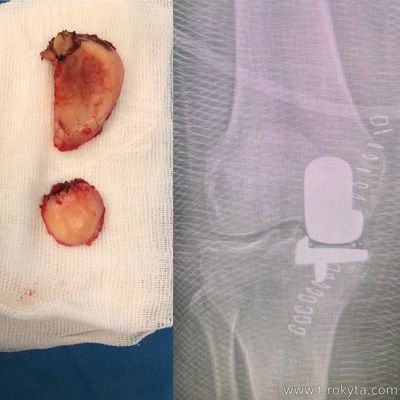

Часткова заміна латеральних відділів колінного суглобу - досить рідка операція. За рік в Україні виконується не більше 5 таких операцій.

Часткова заміна колінного суглобу (або одномищелкове ендопротезування) серед багатьох інших переваг має одну найсуттєвішу - спилюється тільки розрушений хрящ окремої зони і проводиться заміна цієї зони штучним імплантом : |

Ендопротезування латеральних відділів коліна - відносять до досить рідкої патології. За рік таких операцій в Україні виконується не більше 10. Разом з тим, це єдина опція лікування фатальних пошкоджень хряща бокового відділу колінного суглобу. У моїй практиці одномищелкове ендопротезування медіальних відділів коліна досягає до 30-40 за рік, а латеральних - 2. При правильних показах це малотравматична операція з високопозитивним результатом. |